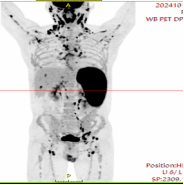

To establish a definitive diagnosis, a lymph node biopsy was performed on Mr. Wu’s right collarbone area. The pathology result indicated “diffuse large B-cell lymphoma" (DLBCL). He was ultimately diagnosed with "non-hodgkin lymphoma, diffuse large B-cell lymphoma complicated by hemophagocytic lymphohistiocytosis (HLH)." A PET/CT scan revealed even more distressing news: lymphoma lesions had involved multiple sites throughout his body, including lymph nodes, the spleen, and several bones (Figure 1). Lymphoma complicated by HLH is clinically a very aggressive and dangerous condition with an extremely high early mortality rate. This diagnosis was undoubtedly a bolt from the blue for Mr. Wu and his entire family.

Figure 1